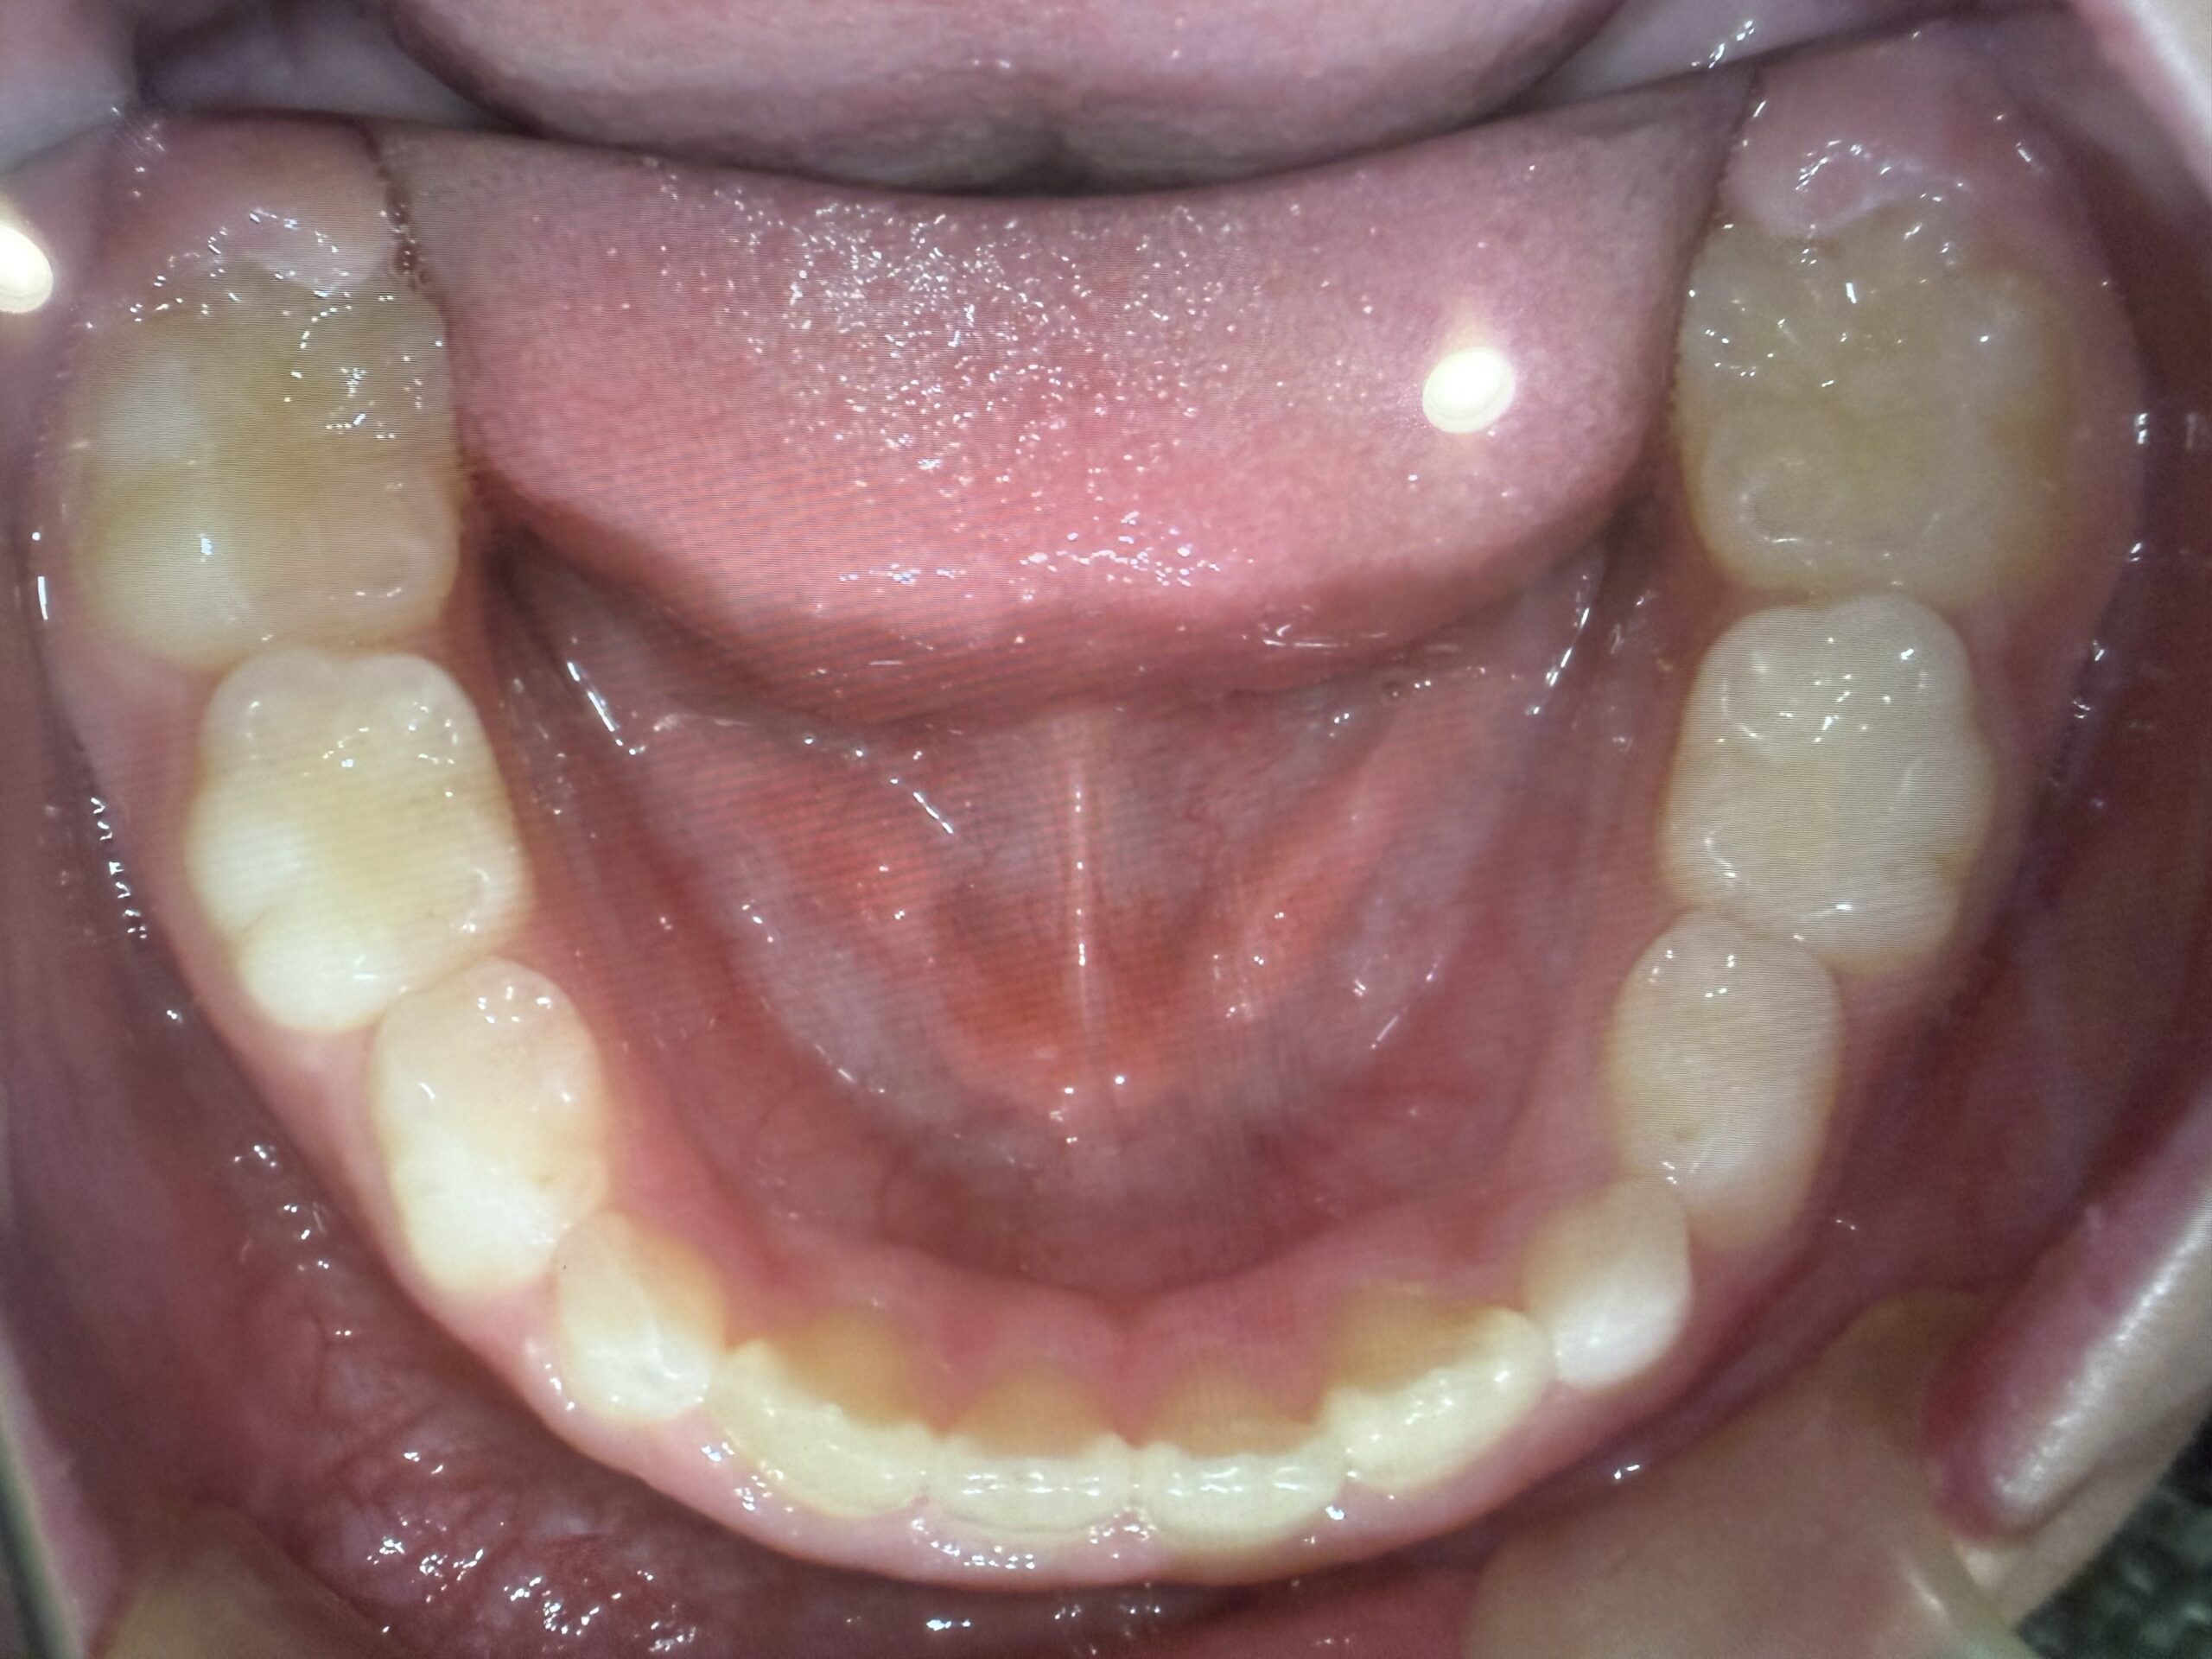

虫歯治療decay

歯周病perio

咬合治療occlusion